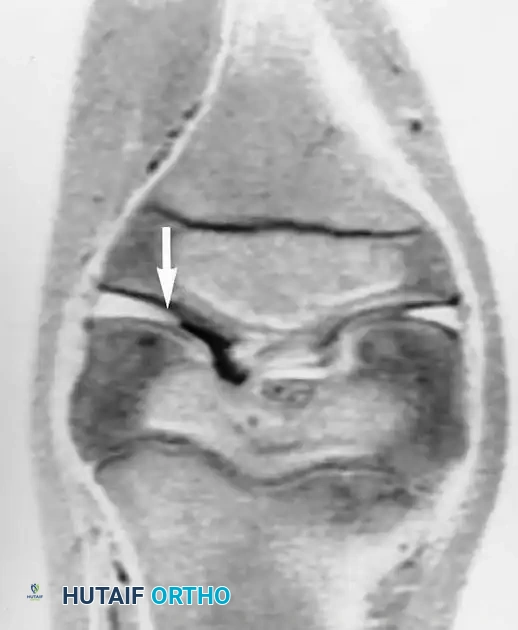

الأكياس الغضروفية والغضروف القرصي

في بعض الأحيان، يصاحب تمزق الغضروف الهلالي تكون أكياس مليئة بالسوائل تسمى الأكياس الغضروفية، والتي تظهر بوضوح في الرنين المغناطيسي.

التمزقات المعقدة والمزاحة

بعض التمزقات تكون شديدة لدرجة أن جزءا من الغضروف ينفصل وينزاح من مكانه الأصلي ليستقر في منتصف المفصل، مثل تمزق يد الدلو، مما يسبب انغلاق الركبة الميكانيكي.

في حالات أخرى، قد ينزاح الجزء الممزق إلى الأسفل تحت الأربطة الجانبية.